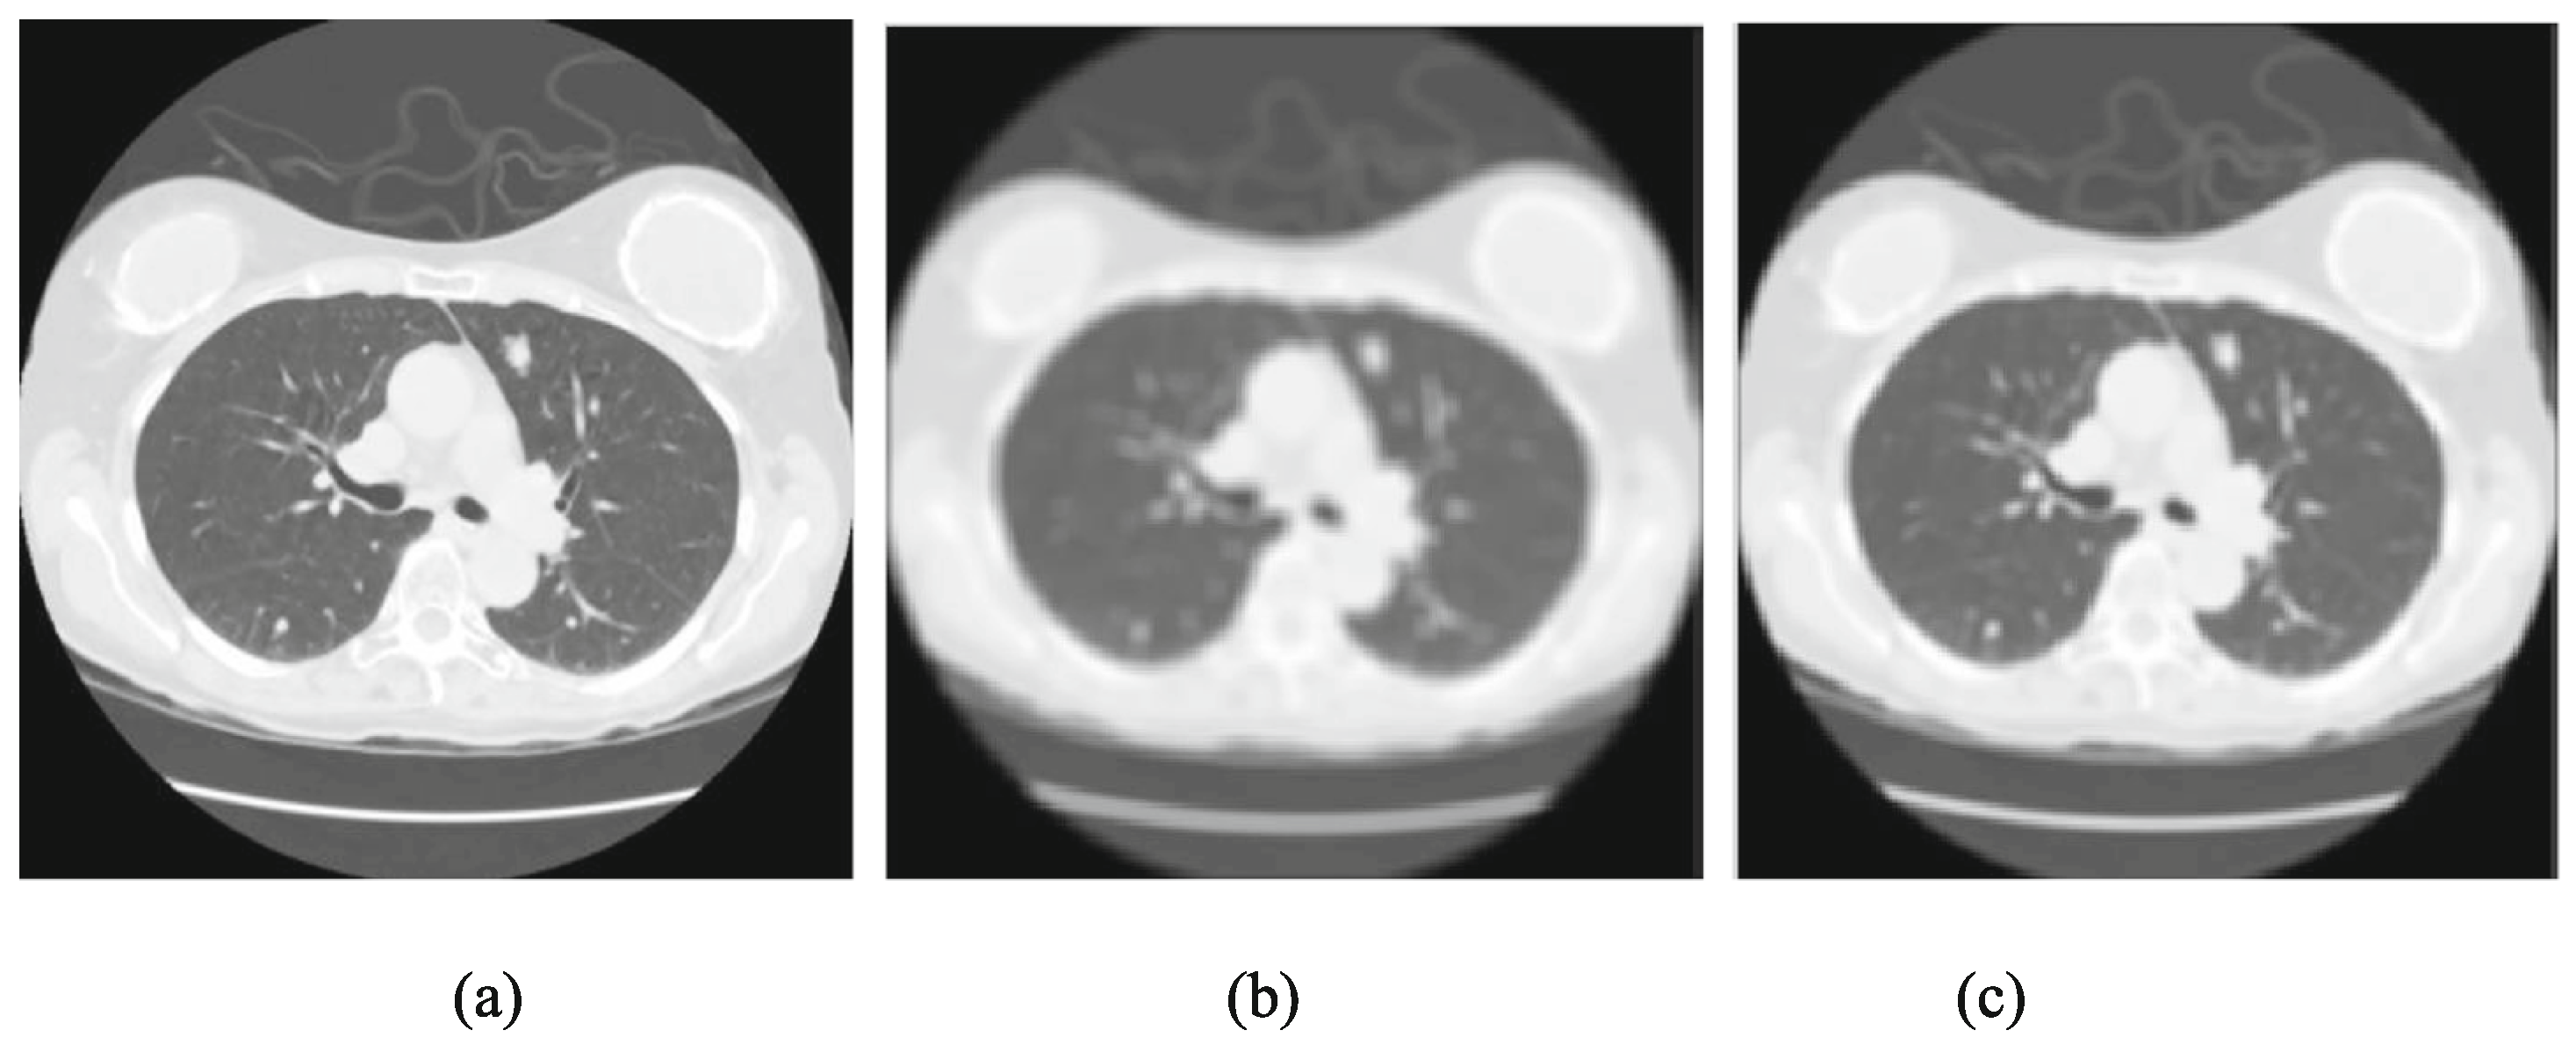

4. Image Preprocessing

- Lei, Y.; Niu, C.; Zhang, J.; Wang, G.; Shan, H. CT image denoising and deblurring with deep learning: Current status and perspectives. IEEE Trans. Radiat. Plasma Med. Sci. 2023, 8, 153–172. [Google Scholar] [CrossRef]